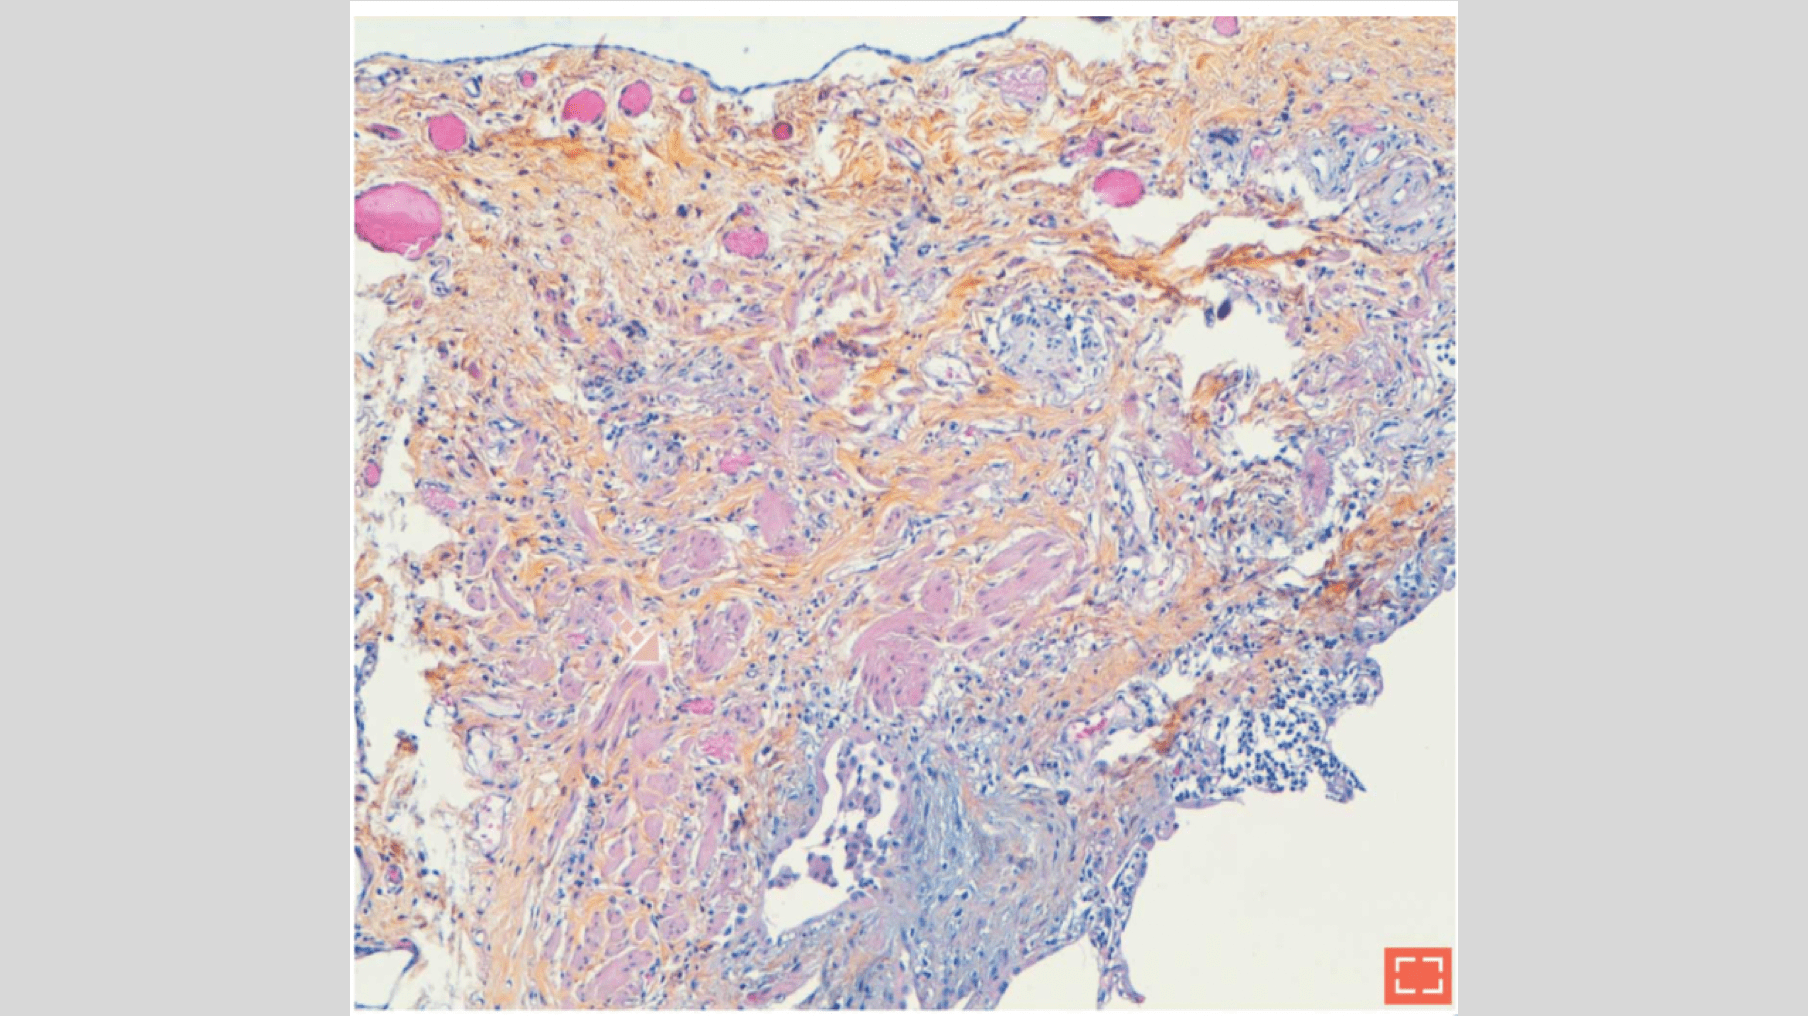

Smooth muscle hyperplasia (II)

Characteristics

• Hyperplastic smooth muscle bundles within subpleural fibrosis

Smooth muscle hyperplasia